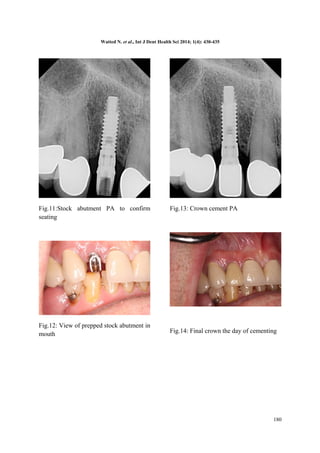

Fig.11:Stock abutment PA to confirm

seating

Fig.12: View of prepped stock abutment in

Fig.13: Crown cement PA

Fig.14: Final crown the day of cementing